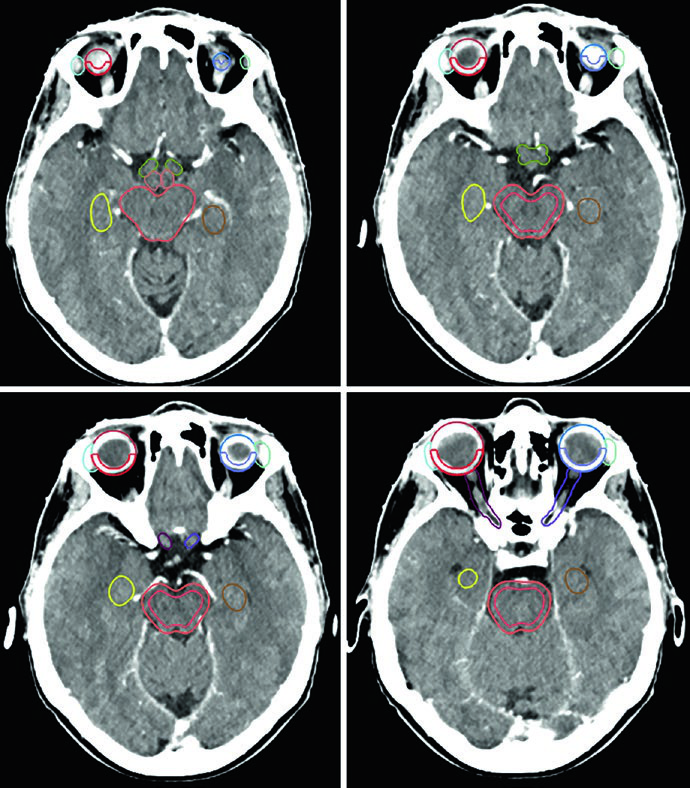

El adenoma secretor de GH de la Figura 29.11 demuestra tratamiento con SRS a 24 Gy. El tumor toca el margen medial de la carótida cavernosa y se extiende lateralmente entre las asas de la carótida, con compromiso del seno cavernoso. La dosis al quiasma, nervios ópticos y tronco encefálico se mantuvo por debajo de 8 Gy. En la Figura 29.12, el adenoma no secretor muestra invasión del seno cavernoso derecho y extensión supraselar — tras la resección, el tumor residual en la silla turca y el seno cavernoso persistió.

La Figura 29.13 muestra la planificación fraccionada del mismo paciente: GTV en coral, CTV con margen de 0,5 cm anatómicamente restringido en teal, PTV con expansión adicional de 0,3 cm. Tronco encefálico, quiasma y nervios ópticos aparecen como OARs delineados. Para macroadenomas, cuando la invasión del seno cavernoso es difícil de visualizar, se recomienda incluir el seno cavernoso completo en el GTV. Conocer el tipo de material implantado en la silla turca (músculo, grasa o colgajo de tabique nasal) ayuda a diferenciarlo del tumor residual.

Un punto práctico fundamental: la evaluación por TC es esencial para decidir si los cambios periósticos y óseos deben incluirse en el GTV. En el ejemplo del meningioma del seno cavernoso (Figura 29.7), el tumor fue delineado con RM de planificación, recibió margen de 2 mm para el PTV y fue tratado a 52,2 Gy en 29 fracciones. Las líneas de isodosis muestran conformación estrecha alrededor del tronco encefálico, quiasma, nervios craneales adyacentes, arteria carótida y cóclea derecha.

Los meningiomas selares y supraselares voluminosos con resección incompleta — como en la Figura 29.8 — pueden requerir expansión de PTV de 3 mm debido a la enfermedad residual extensa. La relación íntima con ambos globos oculares y el tronco encefálico exige una planificación dosimétrica cuidadosa, frecuentemente con IMRT o VMAT para conformar la dosis y proteger estas estructuras críticas.